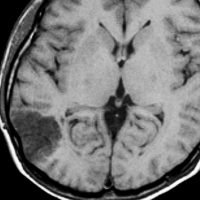

病理は,粘液気質を背景に小型円形の核を有する細胞が増殖し,肺胞用構造を呈していました。その中にやや大型の神経細胞が多数混在するものです。

術前発作期間が長いと症状の回復が不良であるという残念な例でもありました。